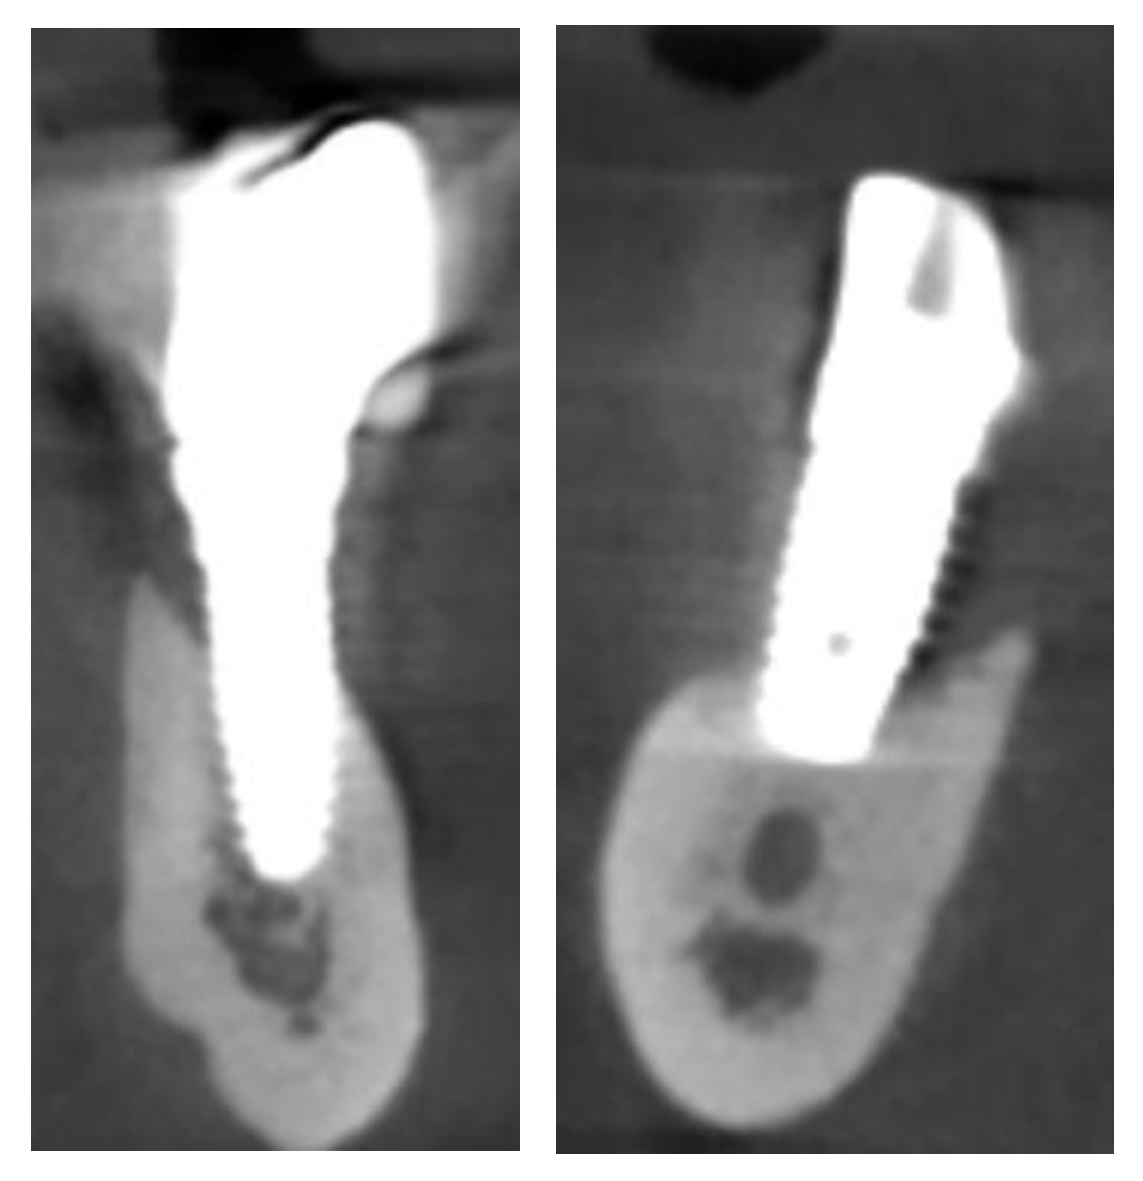

2.1. Planning

Surgical Guide